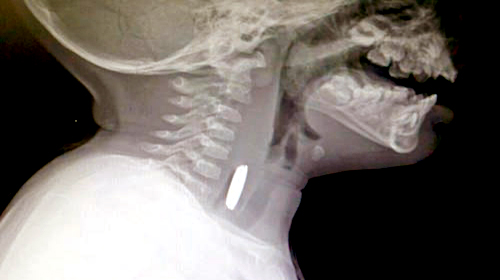

تمكن فريق طبي بمستشفى المجاردة العام بقيادة استشاري جراحة الأنف والأذن والحنجرة والجراحات المجهرية الدكتور محمد عبدالله القرني، من استخراج بطارية صلبة من مريء طفل يبلغ من العمر سنتين.

أوضح ذلك المتحدث الرسمي بصحة عسير بالنيابة سعيد الأحمري. مبيناً: أن الطفل أحضر لطوارئ المستشفى من قبل أسرته بعد ملاحظة عدم قدرته على البلع وتناول الطعام بشكل جيد وأثناء المعاينة وعمل الفحوصات اللازمة، تَبَيّن وجود جسم غريب في المريء؛ وتم نقل المريض إلى غرفة العمليات، وعمل له منظار تحت تأثير المخدر العام.

وأضاف الأحمري, بأن الفريق الطبي نجح باستخراج الجسم الغريب من مريء الطفل الملاصق للأنسجة حيث كان عبارة عن بطارية صلبة، مما استدعى متابعة المريض في العناية المركزة حتى استقرت حالته واستطاع الأكل والشرب. وفي هذا الصدد شدد الدكتور القرني، بضرورة مراقبة الأطفال وعدم العبث واللعب بالأجسام الغريبة الصلبة والحادة بعيداً عن رقابة الأهالي، حفاظاً على سلامتهم.